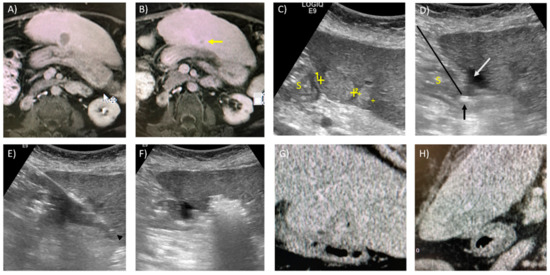

- Kim, T.K.; Khalili, K.; Jang, H.-J. Local ablation therapy with contrast-enhanced ultrasonography for hepatocellular carcinoma: A practical review. Ultrasonography 2015, 34, 235–245. [Google Scholar] [CrossRef] [PubMed][Green Version]

- Dong, Y.; Wang, W.-P.; Gan, Y.-H.; Huang, B.-J.; Ding, H. Radiofrequency ablation guided by contrast-enhanced ultrasound for hepatic malignancies: Preliminary results. Clin. Radiol. 2014, 69, 1129–1135. [Google Scholar] [CrossRef]

- Rajesh, S.; Mukund, A.; Arora, A.; Jain, D.; Sarin, S.K. Contrast-enhanced US-guided Radiofrequency Ablation of Hepatocellular Carcinoma. J. Vasc. Interv. Radiol. 2013, 24, 1235–1240. [Google Scholar] [CrossRef]

- Park, H.S.; Kim, Y.J.; Yu, M.H.; Jung, S.I.; Jeon, H.J. Real-time contrast-enhanced sonographically guided biopsy or radiofrequency ablation of focal liver lesions using perflurobutane microbubbles (sonazoid): Value of Kupffer-phase imaging. J. Ultrasound Med. 2015, 34, 411–421. [Google Scholar] [CrossRef]